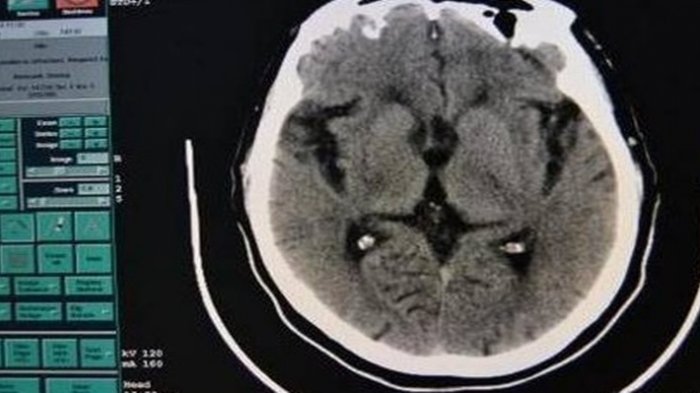

Sedikit informasi, pasien vegetatif adalah kelainan kesadaran ,di mana pasien mengalami kerusakan otak serius yang tidak menunjukkan reaksi kognitif terhadap rangsangan yang ada di sekitarnya.